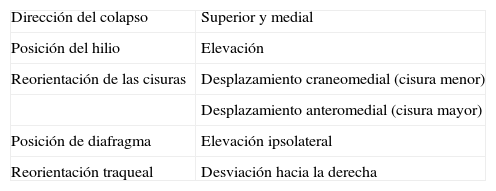

La atelectasia pulmonar es un indicador importante de una enfermedad subyacente, potencialmente grave, que es imprescindible diagnosticar precozmente. Uno de los mecanismos más frecuentes es la reabsorción de aire distal a la obstrucción de las vías respiratorias. La radiografía de tórax es una herramienta excelente para diagnosticarla, especialmente útil para descartar obstrucciones bronquiales centrales (por ejemplo, una neoplasia endobronquial). Si no se reconocen correctamente los signos de la pérdida de volumen el diagnóstico y el tratamiento pueden retrasarse. En este artículo se describen los principales hallazgos radiográficos de la atelectasia pulmonar lobular y su correlación con la tomografía computarizada. Se incluyen los signos clásicos descritos en la bibliografía y otros menos conocidos y a su vez sutiles.

Atelectasis is an important indicator of potentially severe underlying disease that must be diagnosed as early as possible. One of the most common mechanisms is the reabsorption of air distal to respiratory tract obstruction. The chest X-ray is an excellent tool to diagnose atelectasis, and it is especially useful for ruling out central bronchial obstructions (e.g., from endobronchial tumors). If the signs of volume loss are not recognized correctly, the diagnosis and treatment can be delayed. This article describes the main findings of lobar atelectasis on chest X-rays and their correlations with CT findings, including the classic signs described in the literature and other, less known and sometimes subtle signs.